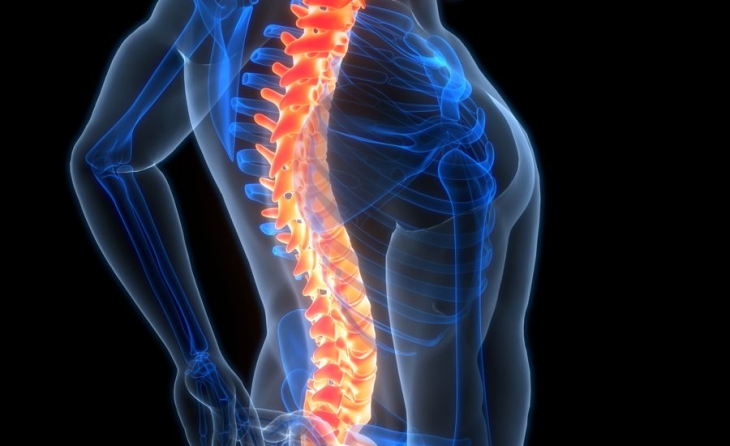

Τι είναι η οσφυϊκή σπονδύλωση

Ο όρος οσφυϊκή σπονδύλωση αναφέρεται στην εκφύλιση των σπονδύλων και των δίσκων στην οσφυϊκή μοίρα της σπονδυλικής στήλης. Είναι μια πάθηση που αφορά άτομα μεγαλύτερης ηλικίας, καθώς είναι συνέπεια της γήρανσης. Η ηλικιακή εκφύλιση δεν συνοδεύεται απαραιτήτως από ανάπτυξη πόνου.

Τι είναι η σπονδυλική στένωση

Η σπονδυλική στένωση είναι μια κατάσταση που προκαλείται από περιορισμό της διαμέτρου του σπονδυλικού καναλιού. Μπορεί να είναι κεντρική ή να περιορίζεται στο επίπεδο των τρημάτων, δηλαδή στο σημείο εξόδου των οσφυϊκών ριζών από το σπονδυλικό κανάλι. Αντίστοιχα υπάρχουν οι όροι κεντρική σπονδυλική στένωση και τρηματική στένωση.

Ποια είναι τα σημεία και συμπτώματα της οσφυϊκής σπονδύλωσης

Τα σημεία και συμπτώματα είναι ανάλογα των στοιχείων που εκφυλίζονται, του βαθμού στένωσης του σπονδυλικού καναλιού και του βαθμού πίεσης των νευρικών δομών.